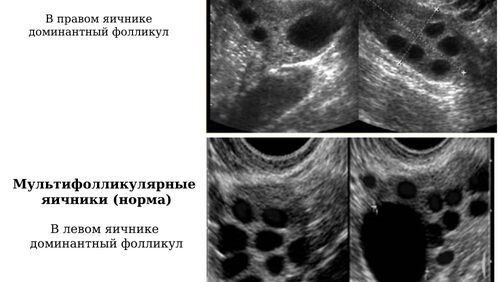

Мульифолликулярные яичники и женское бесплодие. На 1 первом рисунке сверху вниз УЗИ снимок фолликулярного аппарата яичников в норме. Мы видим на снимке три не зрелых и один доминантный фолликул. Это здоровые яичники в которых происходит овуляция и у таких женщин беременность наступает как только она запланирует зачатие. На втором снимке узи картина мультифолликулярных( количество фолликулов больше 10) изменений яичников, мы видим множественное количество фолликулов одного размера и один доминантный т...